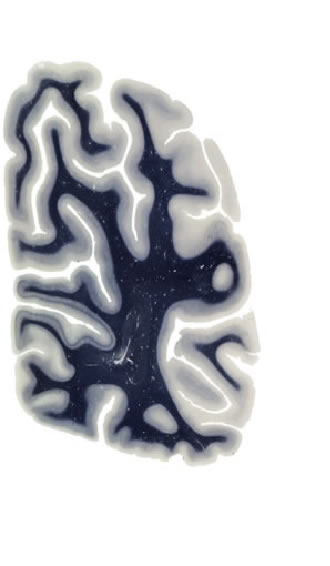

Hi-Resolution Sections · Cells (Nissl Staining) · Virtual Microscopy

Frontal sections (Nissl) from the Atlas Brain:

Slice ID:

r4-1322

Plate NR:

63

Position:

72,5 mm